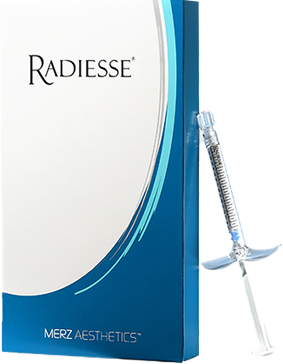

ประกอบไปด้วยคอลลาเจน 70%

ผิวกระชับเปล่งปลั่งทั่วร่างกายด้วยคอลลาเจน ถึง70%